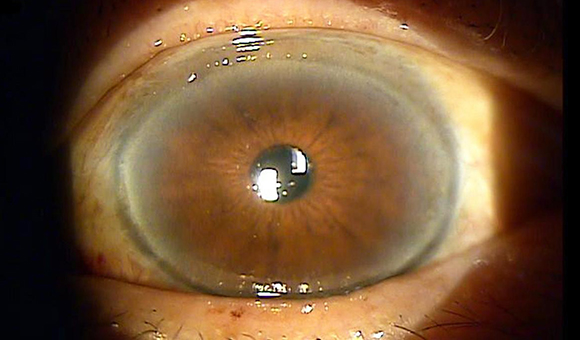

눈 아래 결막의 노출, 안검외반증 수술

이완된 경우 눈물흘림증이나 결막의 충혈, 각막염 등을 유발합니다.

안검외반증 수술의 목적

수술 전

수술 후